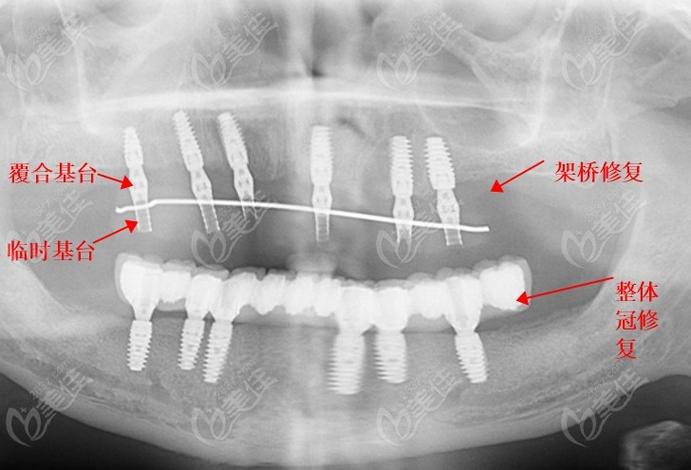

对于全口或半口牙缺失患者,All-on-4/6技术结合种植桥架可实现“当天种植、当天戴牙”的即刻负重效果,该技术通过植入4颗(All-on-4)或6颗(All-on-6)种植体,利用钛合金或氧化锆桥架将种植体连接成整体,上部制作固定义齿,即刻恢复患者咀嚼功能,桥架在此类修复中需具备极高的整体强度和抗变形能力,以支撑全口义齿的长期使用,数字化技术的应用(如术前CBV规划、3D打印桥架)可确保种植体位置精准,桥架与颌骨贴合度达95%以上,大幅提升手术效率和修复效果,尤其适用于希望快速恢复生活质量的患者。